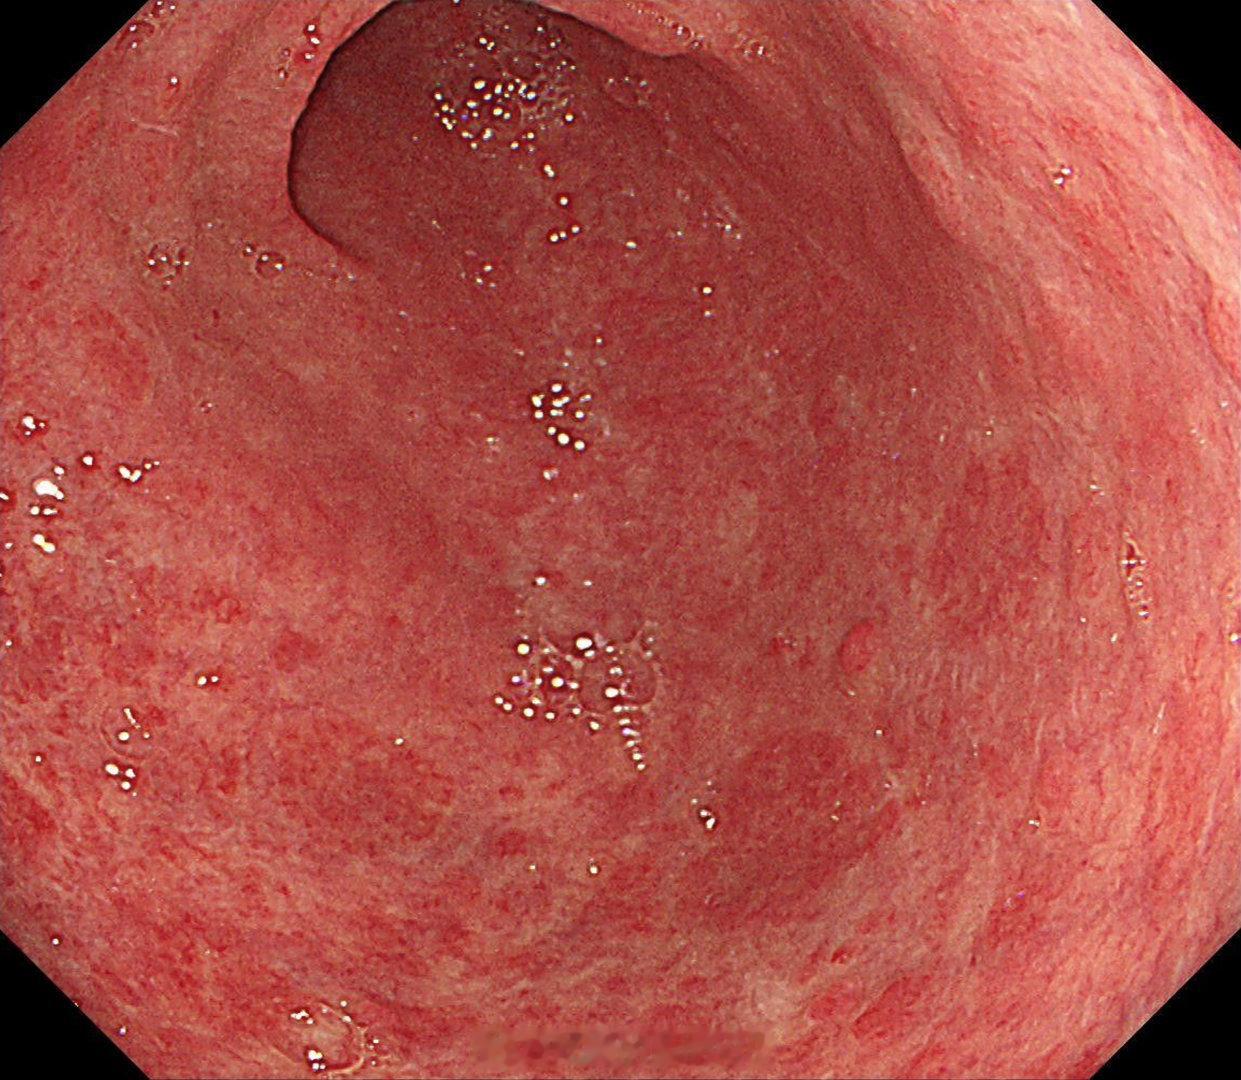

这是个常州来找我会诊的疑难杂症,当地觉得萎缩一塌糊涂,但是活检也没有提示啥病因,一开始我接诊也觉得是自身免疫性胃炎,但是抽血指标都不符合,最后在几块残余正常黏膜表现中看到了点蛛丝马迹,活检加上masson染色确诊是胶原性胃炎,以前不认识的时候这个世界都没这个病,一旦会诊断以后,满眼都是这类病[允悲][允悲][允悲]

这是个常州来找我会诊的疑难杂症,当地觉得萎缩一塌糊涂,但是活检也没有提示啥病因,一开始我接诊也觉得是自身免疫性胃炎,但是抽血指标都不符合,最后在几块残余正常黏膜表现中看到了点蛛丝马迹,活检加上masson染色确诊是胶原性胃炎,以前不认识的时候这个世界都没这个病,一旦会诊断以后,满眼都是这类病[允悲][允悲][允悲]